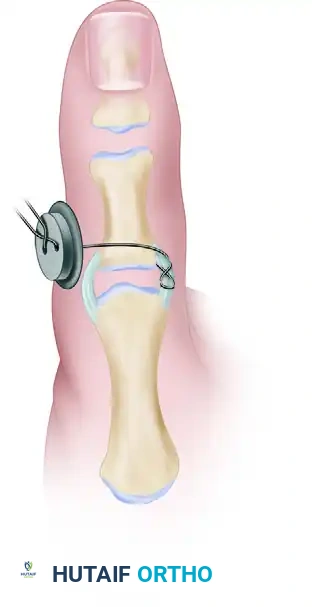

- While holding the joint in slight flexion and applying a gentle ulnar-directed force to reduce the ligament to its footprint, tie the suture ends over a padded button on the radial side of the thumb.

- Pass the twisted pull-out wire loop through the skin near the incision before final closure to facilitate removal in the clinic setting.

- With adequate dorsal exposure, tie this suture directly over the radial aspect of the proximal phalanx bone bridge for permanent placement.

Pitfall: When tying sutures over the radial cortex, ensure that the extensor mechanism and the radial collateral ligament are not inadvertently captured in the knot, which could lead to severe postoperative stiffness.

- Hardware Removal: The pull-out wire (if utilized) and the transarticular Kirschner wire are removed in the clinic at 4 to 6 weeks postoperatively.